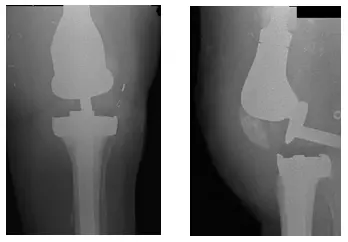

La paciente es una mujer de 75 años que presenta dolor bilateral en la rodilla. Había empeorado sustancialmente el dolor en la rodilla derecha de forma progresiva durante los últimos 6 años. El dolor ha impedido al paciente realizar actividades de la vida diaria,...

El paciente es un varón de 85 años que se presentó con una prótesis tumoral de rodilla izquierda luxada. El paciente llevaba 3 meses en el postoperatorio de una artroplastia total de rodilla (ATC ) con tumor izquierdo Reconstrucción. El paciente requirió cirugía para...

El paciente es un varón de 50 años que acudió quejándose de dolor en la rodilla izquierda. El paciente declaró que se le había practicado una artroplastia total de rodilla izquierda hace unos años en un centro externo. El paciente presentaba una limitación de la...

La paciente es una mujer de 55 años que acudió con dolor en la rodilla derecha. La paciente declaró que se había sometido a un reemplazo total de rodilla derecha hace unos años en una institución externa. El paciente presentaba una limitación grave de la amplitud de...